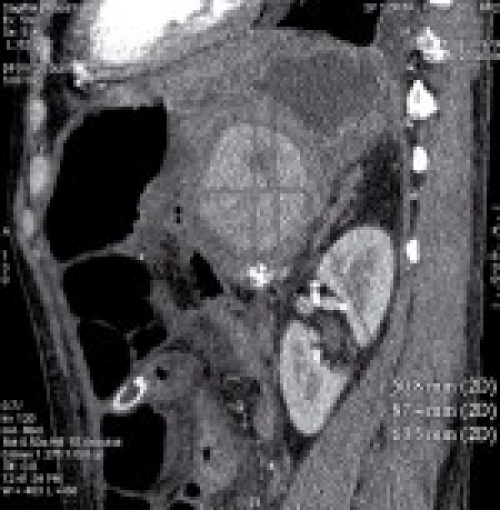

Thermal ablation of unresectable liver tumors: Factors associated with partial ablation and the impact on long-term survival

Philipp Wiggermann, Ralf Puls

DOI: 10.12659/MSM.882463

Med Sci Monit 2012; 18(2): CR88-92

Philipp Wiggermann, Ralf Puls, Andrej Vasilj, Dominik Sieroń, Andreas G. Schreyer, Ernst-Michael Jung, Wojciech Wawrzynek, Christian Stroszczynski